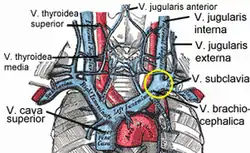

Diagram showing common arrangement of thyroid veins.

Diagram showing common arrangement of thyroid veins. The venæ cavæ and azygos veins, with their tributaries.

The venæ cavæ and azygos veins, with their tributaries.